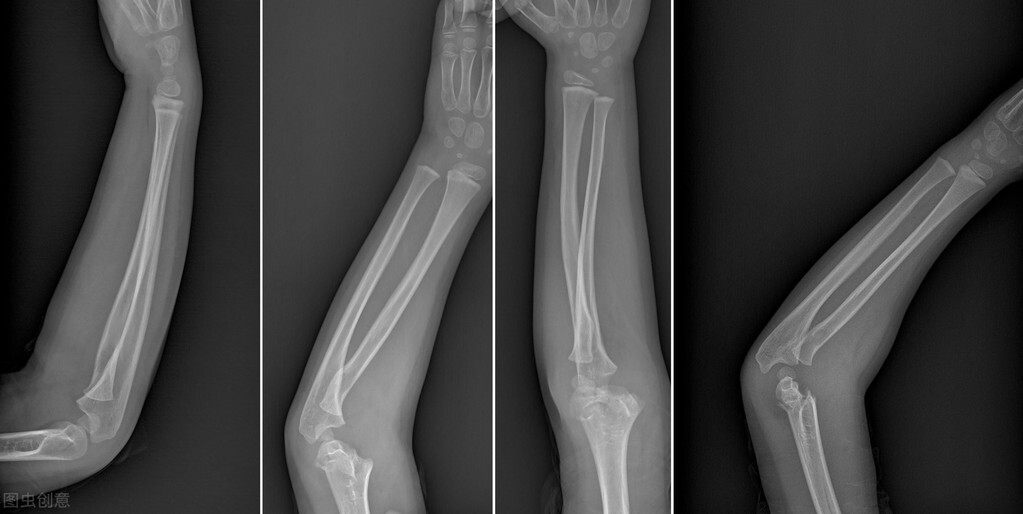

手术以后可以去医院复查三、四次,但是不能常去拍片子(不是说不能拍X光片,要适当、尽量减少拍片的次数),不然对骨折的愈合有碍!具体是否已经骨折愈合,最终要经过拍片决定,还要结合临床检查!

骨折的临床愈合标准

1、骨折局部无压痛以及纵向叩击痛;

2、局部无反常活动;

3、X线片示骨折线模糊,有连续骨痂通过骨折线;

4、外固定解除以后,上肢能满足以下要求:上肢能向前平举1KG重量达一分钟;下肢能在平地、不扶拐的情况下连续步行3分钟,并不少于30步;

5、连续观察两周骨折处不变形。